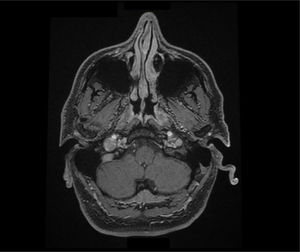

Se completa el estudio con una analítica básica, siendo el hemograma, coagulación y bioquímica incluyendo perfil hepático e iones normales. En la radiografía de tórax no se detectan masas ni ocupación del ápex pulmonar derecho. La TC de cráneo es normal y la angioTC de arterias supraaórticas descarta patología carotídea; sin embargo, se describe una prominencia del golfo de la vena yugular derecha, sin dehiscencia de la lámina ósea, con un foramen yugular prominente (fig. 1). Se completa el estudio con una RM craneal (fig. 2) y medular hasta T1 con contraste, sin detectarse patología a nivel de la vía simpática. Los marcadores tumorales, serología lúes, VIH y Borrelia han sido negativos. Se ha completado el estudio con una TC torácica que descarta patología compresiva o mediastínica.

AngioTC de arterias supraaórticas. A)Se observa una asimetría en el calibre de ambas venas yugulares internas, con mayor diámetro en la vena yugular interna derecha. B)La dilatación se extiende hasta el bulbo yugular. Durante este trayecto, debido a su tamaño, mantiene un estrecho contacto con la arteria carótida interna.

Describimos el caso de un paciente con antecedentes de hipoacusia neurosensorial súbita derecha y tinnitus derecho que presenta años después un síndrome de Horner ipsilateral. En el estudio de imagen se describe un golfo yugular prominente con una asimetría en el calibre de ambas venas yugulares. Observamos en las pruebas de imagen un contacto de la vena yugular derecha (que es más gruesa respecto a la contralateral) con la arteria carótida interna derecha previo a la entrada en el foramen yugular, que podría originar una compresión de la vía simpática a este nivel. Dados los antecedentes del paciente y el estudio de imagen actual, creemos que podrían ser el origen de los síntomas del paciente, en ausencia de otra patología que actualmente lo pueda justificar.